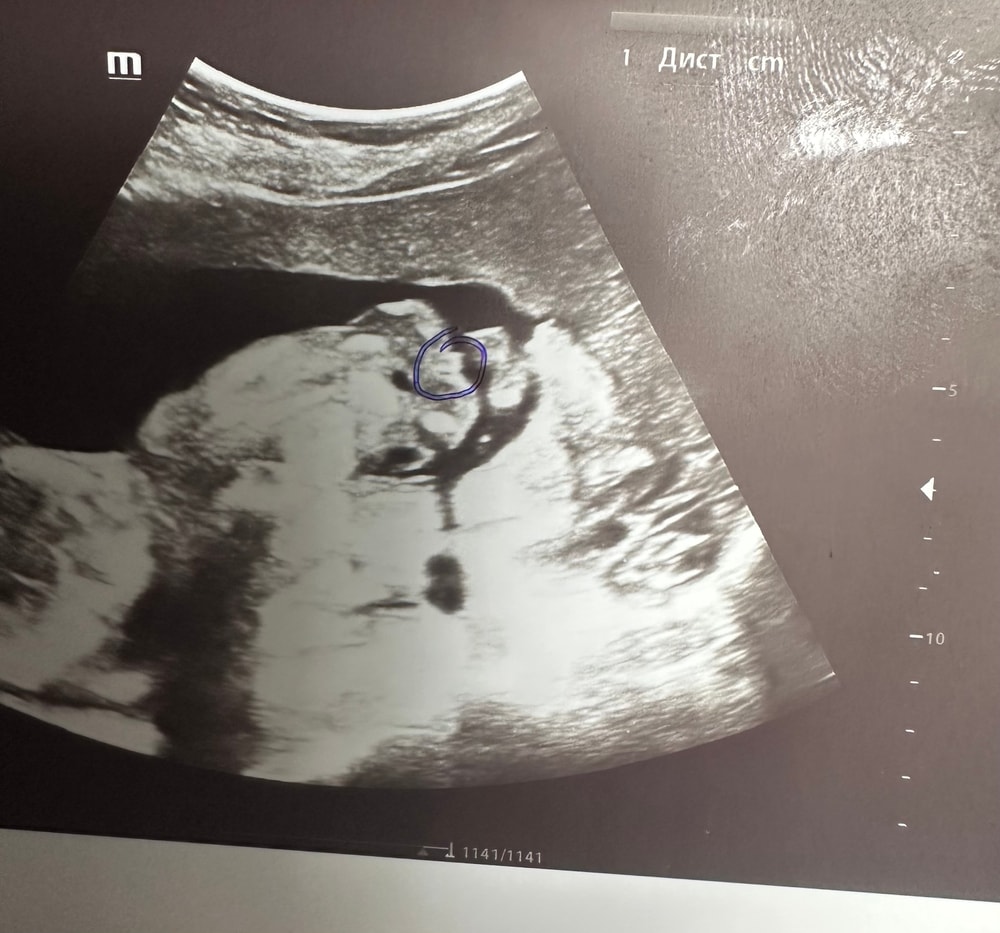

Пол ребенка 16 недель

Пол малышаДоброго времени суток. 16 недель беременности. Предполагают мальчика. Как вы думаете, кого видно по снимку узи? Ребенок расположен спиной, попа видна на снимке и обведено в кружок предположительно машонка ребенка. Но у меня есть сомнения почему-то